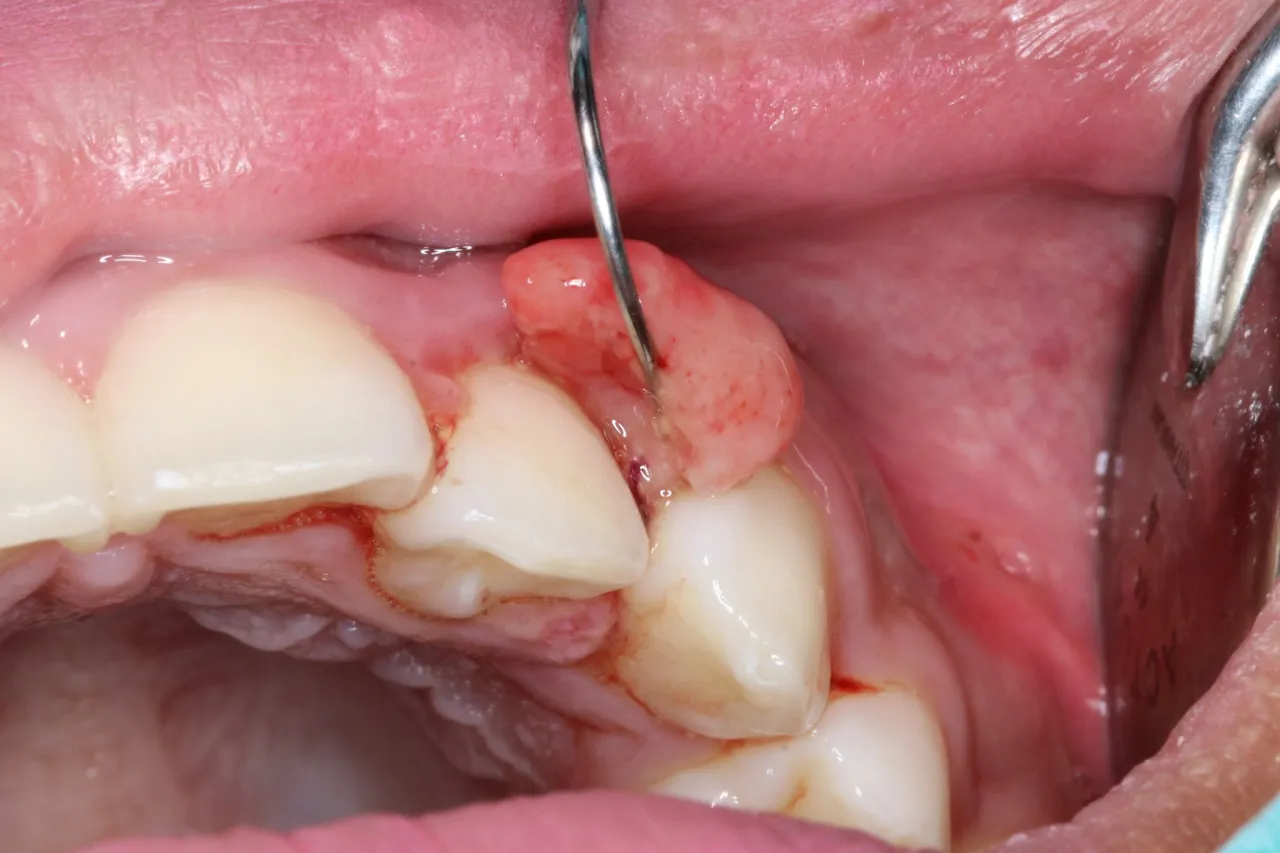

Wizualne cechy raka dziąseł mogą obejmować różnorodne zmiany, które są istotne do zauważenia. Najczęściej nowotwór objawia się jako twardy guzek na dziąśle, który często znajduje się w okolicy zębów trzonowych. Pacjenci opisują te zmiany jako zgrubiałe „kulki”, które mogą powodować dyskomfort. Zmiany te mogą również prowadzić do owrzodzeń, które nie goją się przez dłuższy czas.

W miarę postępu choroby mogą występować inne objawy, takie jak opuchlizna lub krwawienie z dziąseł. W niektórych przypadkach pacjenci doświadczają bólu promieniującego do ucha lub drętwienia wargi dolnej, co może wskazywać na zaawansowaną chorobę. Regularne kontrole u stomatologa są kluczowe dla wczesnego wykrycia tych zmian i rozpoczęcia odpowiedniego leczenia.